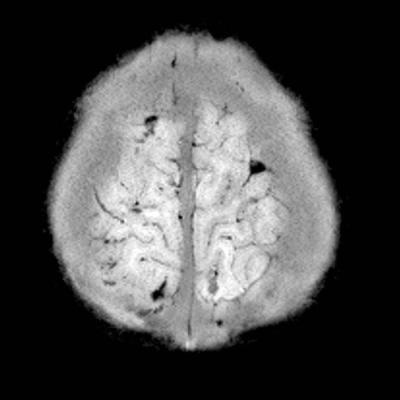

- F) Verteks düzeyinde lolipop/iribaş (tadpole) işareti

- G) Verteks düzeyinde köprü ven trombozuna/yaralanmasına ait duyarlılık artefaktı

- Köprü ven trombozu: Manyetik duyarlılık görüntülemede, kortikal ven trasesinde duyarlılık artefaktı olarak ya da “lolipop” ve “iribaş” (tadpole) işareti şeklinde görülür. Vakaların yaklaşık %30-45’inde saptanır.